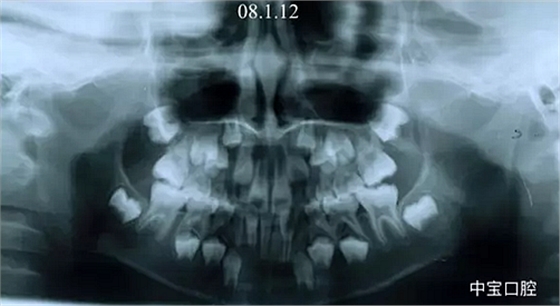

有一個七歲的小女孩,在替牙時媽媽發(fā)現(xiàn)孩子新長的牙不整齊,有一顆長到里面了,上下頜中線也不對稱,很著急就來到門診看牙。

經(jīng)過我臨床檢查和X線的診斷,決定早期干預,每三個月定期復診檢查一次,并拔掉了幾個乳牙和四個恒牙,正畸專業(yè)叫序列拔牙。